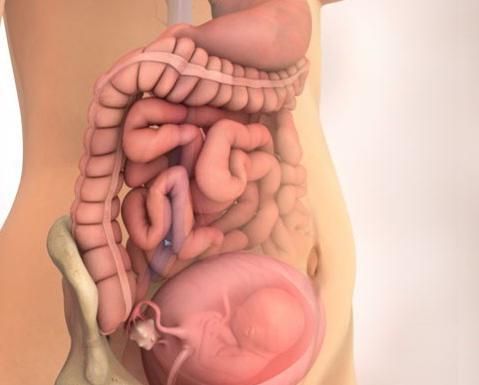

Расположение плода на 15-й неделе беременности: фотографии и иллюстрации

Раздел: Идеи и советы